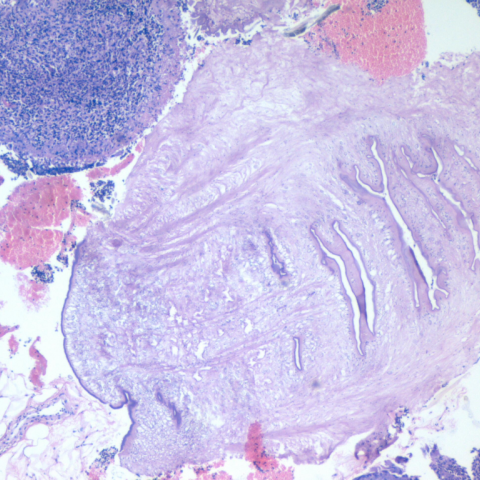

Clinical features depend upon the location of the cyst, number of cysts and host response[3] and a history of residence of travel to endemic region may be helpful. Within soft tissue infestations - subcutaneous lesions may present as painless or painful subcutaneous nodules and intramuscular cysts as myalgia, mass, pseudotumour or pseudohypertrophy. In the breast, an uncommon location of affliction[4-7], it can manifest in the form of a lump ( painful or painless) making the clinical diagnosis a myriad of possibilities ranging from cysts ( simple, complex or complicated) , abscess, fibroadenoma or malignancies to name a few. Radiological investigations are necessary for characterization, defining complications such as cyst rupture or associated abscess formation and image-guided biopsies. Mammogram can reveal masses, lymphadenopathy or even calcied worm-like density[8]. The characteristic finding on an USG is of a complex cyst with a echogenic focus along the wall which represents the scolex. In chronic cases , these lesions tend to calcify. Magnetic resonance Imaging has a role, when the parasite is viable, where peripheral enhancement of the cyst wall can be demonstrated. Definitive diagnosis is made by tissue sampling which reveals presence of a scolex and surrounding host response in the form of inflammatory cell infiltration with histiocytes and epitheloid cell granulomas [9].

An asymptomatic 49-year old lady underwent a screening mammogram [Figure 1.]. In a background of heterogeneously dense breast parenchyma there was a 10mm round mass in the upper-outer quadrant of the left breast (anterior-third) with obscured posterior margins. No calcifications, spiculated mass or significant axillary lymph nodes were noted. She was recalled for further clinical assessment which revealed a palpable lump and an ultrasound (US) was advised. Sonomammogram [Figure 2.], in the area of mammographic abnormality, revealed a 12 x 10mm thick walled cyst with a 2mm polypoidal echogenic mural nodule arising from it’s non dependant wall. No other focal abnormality was seen in the rest of the left breast. Mildly enlarged nodes with slightly thickened cortex were noted in the left axilla. Ultrasound-guided biopsy of the complex cyst was performed [Figure 3.] with no complications. Histopathology [Figure 4] revealed larva of the cysticercal parasite (racemose cyst wall) with a surrounding giant cell reaction. Clinical follow-up after a two-month course of albendazole showed no palpable abnormality and USG [Figure 5.] in the region of abnormality showed resolution of the cyst.